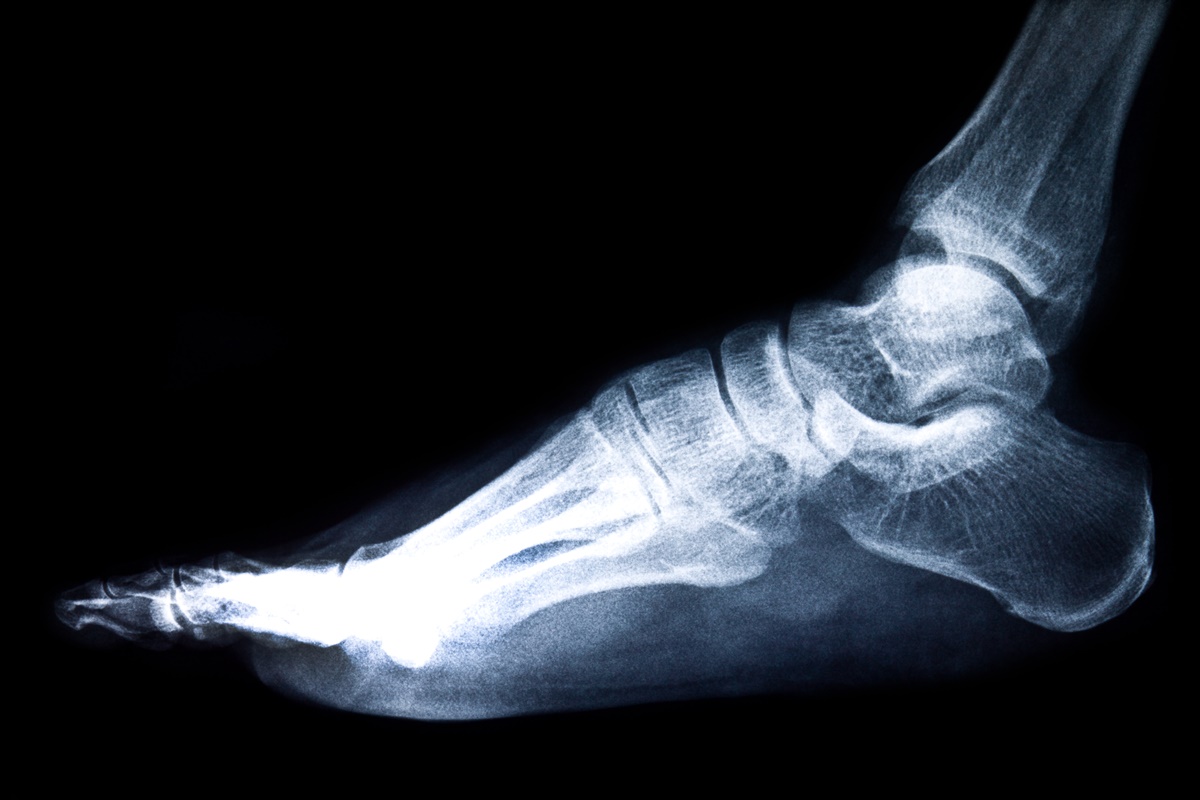

กระดูกงอก คืออะไร?

รศ.นพ.บวรฤทธิ์ จักรไพวงศ์ ภาควิชาศัลยศาสตร์ออร์โธปิดิคส์และกายภาพบำบัด คณะแพทยศาสตร์ศิริราชพยาบาล มหาวิทยาลัยมหิดล ระบุว่า กระดูกงอก คือกระดูกที่งอกเกินขึ้นมา อาจจะงอกเกินมาตั้งแต่กำหนด สัมพันธ์กับการเป็นคนมีเท้าแบน (ไม่มีอุ้งเท้า) หรืออาจเกิดจากที่เท้าบาดเจ็บจากการใช้งานหนักหรือผิดท่า แล้วกระดูกมีการซ่อมแซมตัวเองที่ไม่ดีนัก โดยกระดูกที่งอกขึ้นมาใหม่อาจเสียดสีกับเส้นเอ็นที่เท้า ทำให้บาดเจ็บได้ และร่างกายอาจจะซ่อมแซมด้วยตัวเองได้ยาก

คนที่มีเท้าแบนอาจมีปัญหากับเอ็นร้อยหวายได้ด้วยเหมือนกัน เพราะเอ็นร้อยหวายจะตึงมากกว่าคนทั่วไป แม้จะมีข้อดีที่จะทำให้ข้อเท้ายืดหยุ่นได้ดี กระโดดได้สูง หรือวิ่งได้เร็ว แต่เอ็นร้อยหวายก็จะเปราะ และบาดเจ็บได้ง่ายมากกว่าคนทั่วไปเช่นกัน แต่หากได้รับคำแนะนำ หรือการฝึกฝนจากแพทย์ผู้เชี่ยวชาญที่ดี ก็จะสามารถใช้ประโยชน์ในเรื่องนี้ได้มาก และปลอดภัยต่อสุขภาพขาและข้อเท้าได้

หากพบขนาดของกระดูกงอกไม่ใหญ่ ไม่ทำให้เกิดอาการบาดเจ็บ ก็ไม่มีความจำเป็นต้องเข้ารับการผ่าตัด แต่อาจจะให้คำแนะนำในการบริหารยืดหยุ่นเอ็นร้อยหวายเพื่อลดอาการบาดเจ็บในอนาคต

หากได้รับการผ่าตัดแล้ว ผู้ป่วยอาจจะยังมีอาการเจ็บบริเวณที่ผ่าตัดอยู่เล็กน้อย แพทย์จะแนะนำให้นวดคลึงบริเวณที่เคยผ่าตัดเบาๆ รวมถึงเขย่งบ่อยๆ เพื่อคลายผังผืดที่อาจเกิดขึ้นหลังผ่าตัด และทำให้กล้ามเนื้อกลับมาทำงานได้ตามปกติ